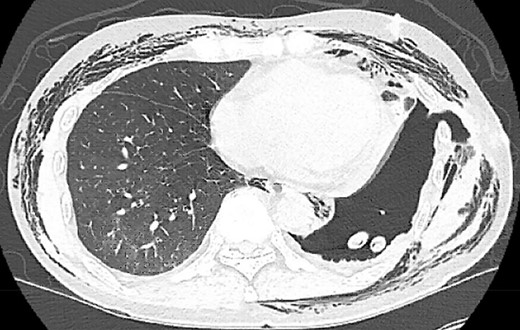

Postoperatively, the patient developed persistent expiratory air leak and thus underwent left VATS mechanical and chemical pleurodesis with Doxycycline on POD 4. Air leaks observed at previous staple lines were reinforced with additional staple loads, Floseal and Progel. In addition, an apical pleural tent was performed in the left upper lobe. He continued to have an expiratory air leak. Imaging on POD 13 demonstrated a BPF communicating with the pleural space (Fig. 2). Bedside pleurodesis with Doxycycline was performed through the thoracostomy tube.

POD13 CT scan demonstrating a BPF between the fifth and sixth ribs communicating with a pneumothorax and subcutaneous emphysema.